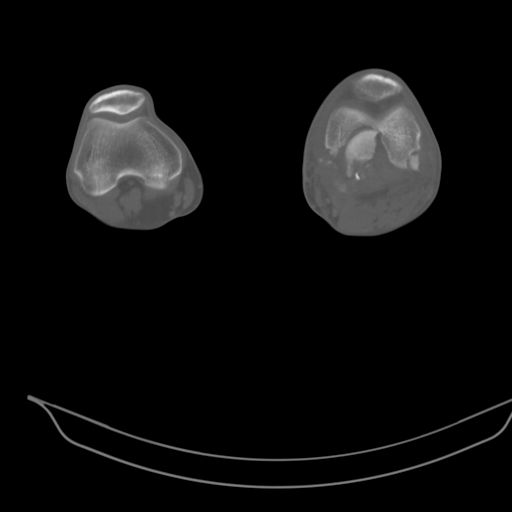

CT shows major bony fragments which are markedly rotated .With this amount of bony damage,you probably should attempt to get reasonably loooking knee with ORIF and thn if he needs a TKR due to pain a few years from now, then tleast you have something looking like a knee that you can replace rather than having to use revision knee for a primary TKR now. 4 weeks is not too long .what is the condition of soft tissues?

При внутрисуcтавных переломах трехмерные (3D) изображения, кроме красивого снимка, не дают полную информацию о состоянии отломков, самыми информативными являются корональные срезы на КТ и обычная длинная ренгенограмма конечности для сравнения оси конечности.